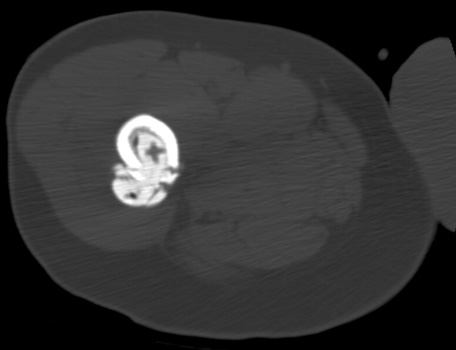

Cement extravasation in the thigh through intraoperative

fracture at the level of the tip of the femoral stem.